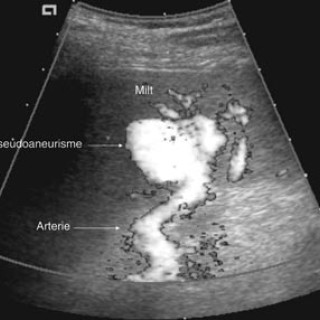

Myiasis (av gresk «myia», flue) foreligger når mennesker eller dyr angripes av fluelarver som ernærer seg på levende eller dødt kroppsvev. En rekke fluearter kan forårsake myiasis i hud, nasopharynx, øyne og gastrointestinal- eller urogenitaltractus (1). Den kutane form er langt den vanligste. I Norge er disse tilstandene sjeldne, men med økende reiseaktivitet vil vi av og til møte pasienter med sykdommen. Pasienten. En 43 år gammel norsk mann fikk under en to ukers reise i Amazonas, Brasil, tre «flåttbitt» på henholdsvis underekstremiteter og på halsen. Bittene på underekstremitetene tilhelet...